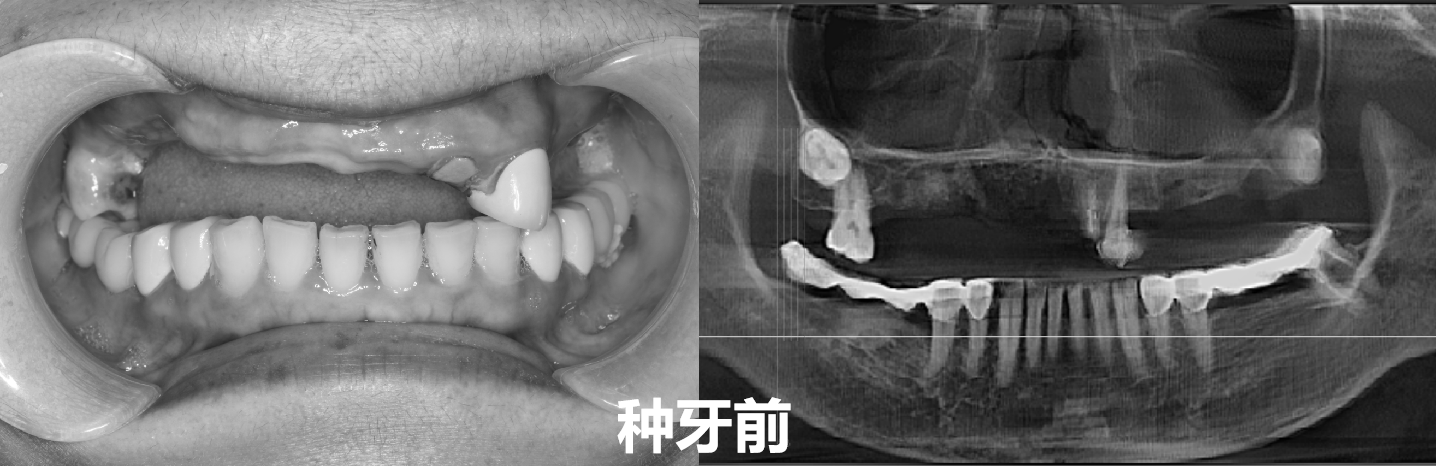

谢阿姨今年56岁 , 但她的牙齿表现的年龄却远不止如此 。 上颌仅剩1颗真牙、1颗烤瓷牙冠;下颌大部分磨牙也都换成了烤瓷牙 , 只有前牙还在 。 这样的牙齿状况即使跟70多岁的人相比也不一定更好 。 这也告诉人们 , 养成良好的口腔习惯、日常生活中注意保护牙齿的重要性 。

最初做的是活动牙 , 从三颗牙冠到五颗牙冠 , 从一侧到两侧 , 活动牙换过不知道多少次 。 但能感受到的力量越来越小 , 吸附性也越来越差 。 拍片检查才知道 , 由于缺牙时间太长 , 从最初缺牙的位置开始 , 上颌牙槽骨出现了较重的萎缩吸收 。

大约五年前 , 谢阿姨的上颌牙已经脱落只剩四颗 , 而下牙也脱落了两个大牙 。 因为活动牙已经不能提供足够的咬合力 , 谢阿姨听了医生的建议 , 全部做了烤瓷牙 。 从那之后的两三年 , 谢阿姨又找回了好牙好生活的感觉 。 相比之前的活动牙 , 烤瓷牙固定修复确实更有力量 , 也稳固了许多 。